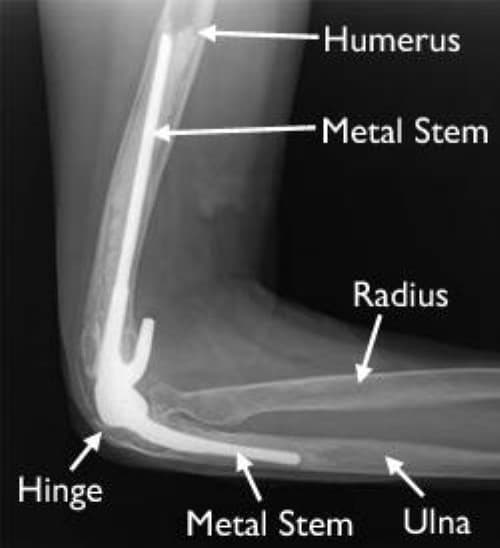

Тохойн хиймэл үе солих мэс засал

Тохойн үе нь бугалга, шуу, богтос яснаас бүрдсэн үе юм. Яс эргэшгүй өөрчлөлтөд орсон, өвдөлт зовиур мэс заслын бус эмчилгээнд үр дүнгүй үед тусгай зориулалтын хиймэл үе/эндодротез/-р солих мэс засал хийнэ.

Тохойн хиймэл үе солих мэс засал image1